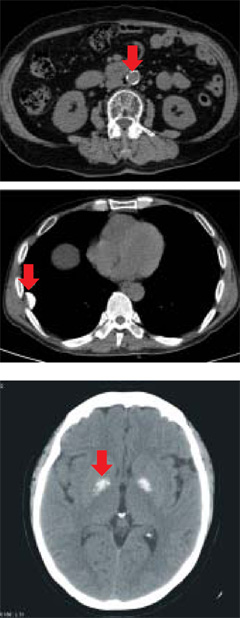

석회질은 CT 사진에서 하얀 돌처럼 보인다. 사진 위부터 복부대동맥·폐·뇌에 생긴 석회질. /중앙대병원·아주대병원 제공

암일 수 있는 유방·갑상선·뇌 석회질= 중앙대병원 내분비내과 안지현 교수는 "석회질이 있는 갑상선결절은 암 가능성이 다른 갑상선결절보다 4~9배 높고, 유방 석회질의 10%는 유방암"이라고 말했다. 아주대병원 신경외과 조진모 교수는 "뇌의 석회질은 대부분 노화 현상이지만, 5% 정도는 암으로 발전하기도 한다"고 말했다. 갑상선과 유방 석회질은 처음 발견한 뒤 3~6개월 후, 뇌 석회질은 1년 후에 다시 검사해서 크기가 자라거나 개수가 많아지면 암을 의심하고 조직검사를 한다.